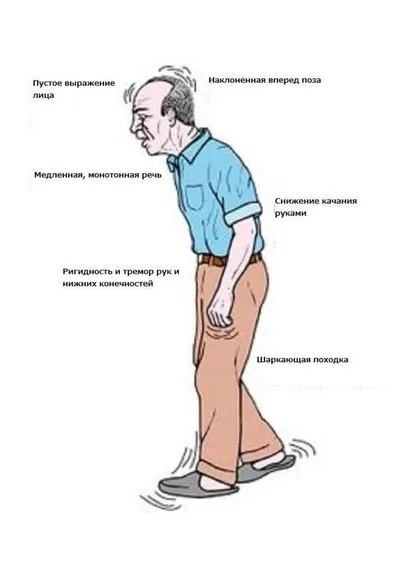

ЦНС, головной мозг оказывается под токсическим воздействием первыми. Наркотические вещества влияют на центры, нервные ткани, вызывают метаболические нарушения, сказываются на кровообращении. Частыми спутниками зависимых становятся:

- Хронические расстройства мозговой трофики. Сосуды сужаются и не могут поставлять достаточное количество питательных веществ и кислорода. С течением времени развивается энцефалопатия — хроническое дистрофическое нарушение ЦНС, слабоумие, расстройствам высшей нервной деятельности.

- Энцефалопатия — собирательное название дистрофий нервной ткани. Развиваются постепенно, отличаются стойкостью, с трудом поддаются лечению, особенно на поздних стадиях патологии.

- Острые ишемические процессы. Складываются у пациентов на поздней стадии (если есть склонность к неотложным состояниям, факторы риска — в любой момент). Речь об инсульте, транзиторных ишемических атаках. Заболевания потенциально смертельны, приводят к неврологическому дефициту.

- Деменция. Закономерный результат энцефалопатии, недостаточного кровообращения. Патологическое состояние сопровождается выраженными нарушениями мозговой активности, мышления, внимания и памяти. Почти не поддаётся терапии, только частичной коррекции.

Симптомы неврологических расстройств на ранних этапах скудные: забывчивость, повышенная утомляемость, головные боли, головокружения. По мере прогрессирования присоединяются новые признаки. Лечением осложнений ЦНС занимаются врачи-неврологи (невропатологи), нейрохирурги, реабилитологи. Применяют ноотропные препараты, цереброваскулярные средства, витаминные комплексы, в некоторых случаях — стимуляторы. Прогнозы зависят от стажа аддикции, типа патологии. Без качественной коррекции шансов на восстановление нет.